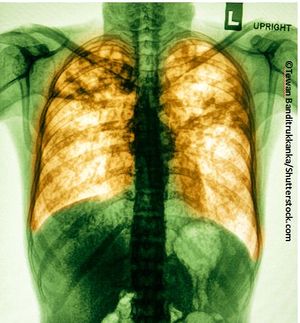

Once again, the USPSTF finds no net benefit to screening asymptomatic persons for COPD. Draft recommendation is available for comment.